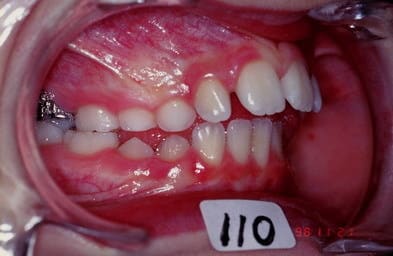

cas n 2

classe II 1 avec pouce

QH + Ecran cuccal pendant 4 mois seulement separent les photos